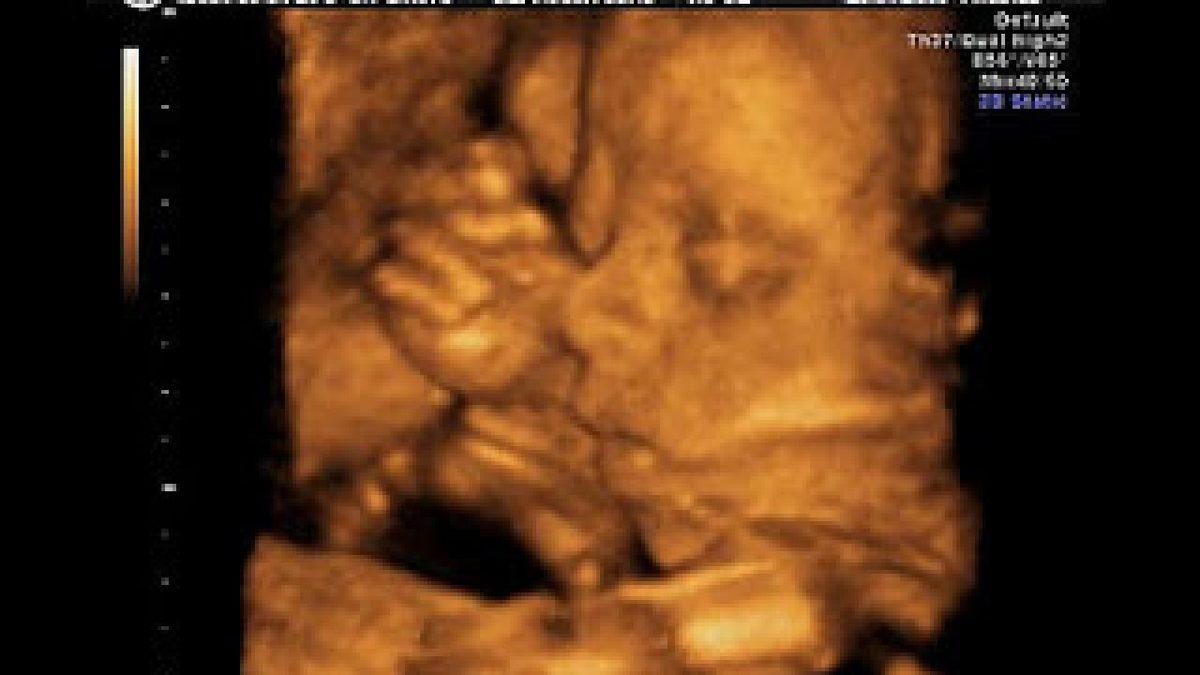

3 ya da 4 boyutlu ultrason:

Gebe kadınlara bebek dış yüzeyinde önemli bir sorun tespit edilmeden 3 ya da 4 boyutlu ultrason uygulanmaz. Ancak doğuma kadar sabredemeyen aileler, bebeklerinin elini, kolunu, ayağını, bacağını, yüzünü hatta gülüşünü görmek için bu ultrason türünü isteyebilirler. Bu ultrason türü ile bebeğin cinsiyeti de kolayca tespit edilebilir. Ancak zorunlu bir işlem olmadığı için diğer ultrason çeşitlerine göre uygulaması daha pahalı bir türdür.